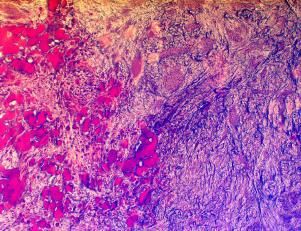

Visuel Cordon ombilical

Les formidables pouvoirs du cordon ombilical

Rencontre avec Anaïs Lavrand, doctorante au laboratoire BIOS (oct. 2025)